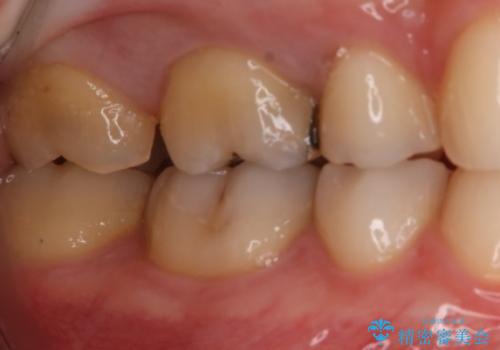

- 右上大臼歯の再治療を希望され来院された患者様です。

切削量と形状を考慮し、インレーでの治療を計画しました。

患者様がゴールドを希望されたのでゴールドインレーを選択しました。

ゴールドは金属の中でも硬すぎず破折すこともほとんどないため歯科の治療に適した材料と言われています。